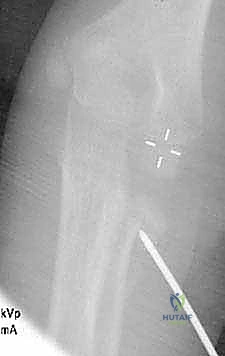

صورة شعاعية توضح كسراً من الدرجة الثالثة يتطلب تدخلاً دقيقاً لإعادة الرأس الكعبري إلى مساره التشريحي.

استخدام الأشعة السينية لتحديد زاوية الميلان بدقة قبل اتخاذ القرار العلاجي.